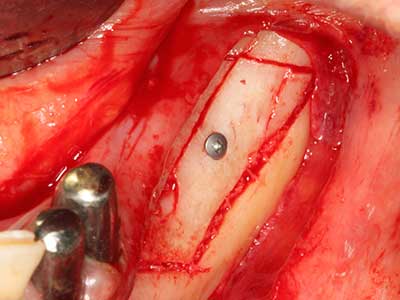

Como ya se ha demostrado en el pasado, básicamente cualquier procedimiento de cirugía de hueso representa una posible indicación para la cirugía piezoeléctrica. Así, la preparación del segmento móvil en la osteogénesis de distracción (fig. 23-25) y en la osteotomía de sándwich puede realizarse con piezas especiales, sin poner en peligro el suministro sanguíneo de la parte crestal, que resulta esencial para el éxito de ambas técnicas (González-García, Diniz-Freitas et al. 2008).

Para la extracción de implantes es posible realizar la preparación de una tapa ósea vestibular que, tras retirar el tornillo del implante, vuelve a fijarse y, de este modo, mantiene el contorno de la apófisis alveolar.

En la cirugía del seno maxilar surgen otros campos de aplicación: En este punto, tras la preparación concéntrica de una tapa ósea de la pared del seno maxilar (que suele tener forma trapezoidal), es posible eliminar patologías y cuerpos extraños del seno maxilar. La tapa ósea se repone después de finalizar la parte intra-antral de la operación y se asegura frente a una posible dislocación mediante cuñas o suturas adaptables.